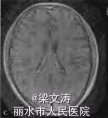

体温38.1℃,意识清楚,定向力、记忆力、计算力等高级皮质功能明显受损;脑神经阴性;四肢肌力V级,肌张力正常,腱反射(++),两侧对称;双侧巴氏征阴性,脑膜刺激征阴性。共济运动及感觉系统查体不能配合。全身浅表淋巴结未触及肿大,两肺未闻及干湿性啰音,心律齐,腹平软,肝脾肋下未触及,双下肢无水肿。血常规示三系减低:白细胞计数3.6 X10^9/L(参考范围:4.0 X 10^9/L一10.0×10^9/L),红细胞计数2.15×10^12/L(参考范围:4.00×10/L一5.50×10^12/L),血小板计数68×10^9/L(参考范围:100×10^9/L一300×109/L)],低蛋白血症[清蛋白28.5 g/L(参考范围:35.0一52.0g/L)];红细胞沉降率、肝肾功能及电解质均正常,维生素B、叶酸正常,3次血培养均阴性;艾滋病抗体阴性;抗核抗体、肿瘤标志物、自身抗体及抗中性粒细胞胞质抗体(ANCA)阴性,免疫球蛋白M轻度降低[0.28 g/L(参考范围:0.46—3.04 g/L)];乳酸脱氢酶[1 120 U/L(参考范围:135—225 U/L)]和血13:微球蛋白[3.7 mg/L(参考范围:1.0—2.5 zng/L)]明显增高。腰椎穿刺脑脊液检查示:压力150 illln H20(参考范围:80-180mmH20,1 mm H20=0.0098 kPa),白细胞计数7×10*6/L[参考范围:(0—10)X100/L],蛋白2.80 g/L(参考范围:0.10—0.25 g/L),氯离子:107 mmol/L(参考范围:120—130 mmol/L),糖3.5 mmol/L(参考范围:2.5~4.5 mmol/L);细胞学正常;IgG指数0.099;JCV—DNA阳性;单疱病毒、柯萨奇病毒、埃可病毒、巨细胞病毒等抗体阴性;墨汁染色阴性,细菌加真菌培养阴性。2.3影像学检查2009-12-25腹部CT提示脾脏偏大,2010-01-12复查腹部CT提示脾脏肿大、两侧肾上腺区团块影。2009-12-29颅脑MRI示两侧半卵圆中心、侧脑室旁多发病变009—12—24骨髓穿刺检查示有核细胞增生活跃,红系/粒系(G/E)=0.87:1;中性粒细胞增生(占40.4%),以中性中间阶段粒细胞为主;红细胞增生(占46.4%),以中晚幼红细胞为主;淋巴细胞比例下降;血小板计数较少,吞噬细胞增多,未见明显异常细胞,CD3、CD8、CD4、CD16、CD56均正常。

患者2009—12—27入住感染科,予头孢哌酮针及阿奇霉素针抗感染等治疗,病情无明显好转。2009—12—29行颅脑MPd检查示脑内多发脱髓鞘样病灶,于2010—01—06转入神经内科并行相关检查。根据该患者的临床和影像学特征,结合脑脊液中JCV的DNA序列检测以及骨髓穿刺病理活检结果,诊断为弥漫大B细胞淋巴瘤并发PML可能。虽经退热、补液,纠正贫血、低蛋白血症等积极治疗,但患者病情仍迅速进展,于2010—01—28凌晨出现呼吸、心搏停止,予气管插管、心肺复苏等积极抢救治疗后呼吸、心搏恢复。患者自动出院1 d后死亡,家属拒绝尸检

本例患者表现为视觉障碍、认知功能减退和精神行为异常等典型的PML症状,颅脑MRI检查符合典型的PML影像学表现;脑脊液中检测到JCV的DNA序列,病理活检证实弥漫大B细胞淋巴瘤侵犯骨髓,并且缺少其他感染或肿瘤的依据。因此,本例患者诊断为弥漫大B细胞淋巴瘤并发PML。PML患者通常处于免疫抑制状态,在此基础上需要与其他颅内多发病灶鉴别,如中枢神经系统血管炎、原发性中枢神经系统淋巴瘤以及脑弓形体病等。本例患者病史和实验室检查以及颅脑MRI表现均不支持以上疾病的诊断。目前,针对PML尚无特异的治疗措施,PML患者的预后极差,临床需引起足够的重视。当存在免疫缺陷或免疫抑制的患者出现典型的视觉障碍、认知功能改变、肌无力等症状时,应考虑本病的可能。本例患者虽经积极对症治疗,但患者病情仍迅速进展、恶化。因此,在病程早期行颅脑MRI检查以及腰椎穿刺脑脊液检测JCV的DNA序列,均有助于本病的诊断,必要时可行脑组织活检。明确诊断后应立即开始免疫重建治疗,抑制脱髓鞘的继续进展;同时避免医源性PML也非常重要。